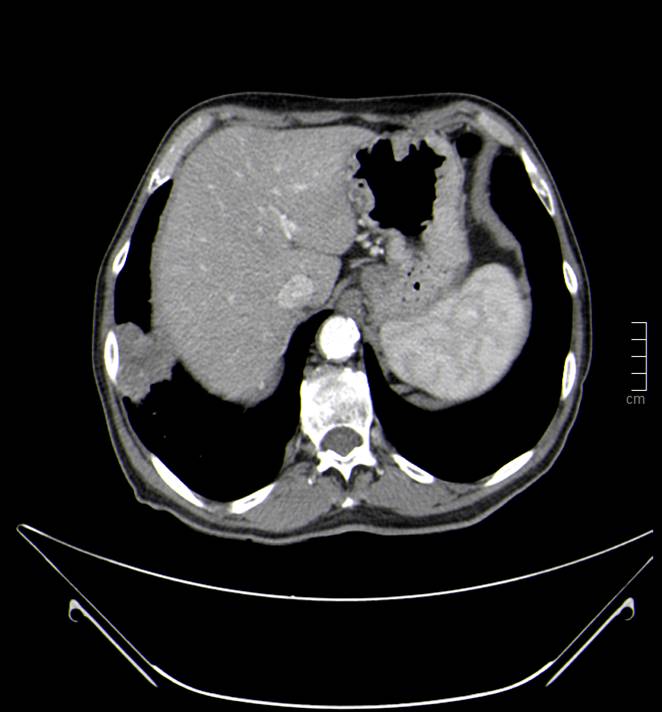

Masa en lóbulo inferior derecho (LID), compatible con neoplasia primaria pulmonar.